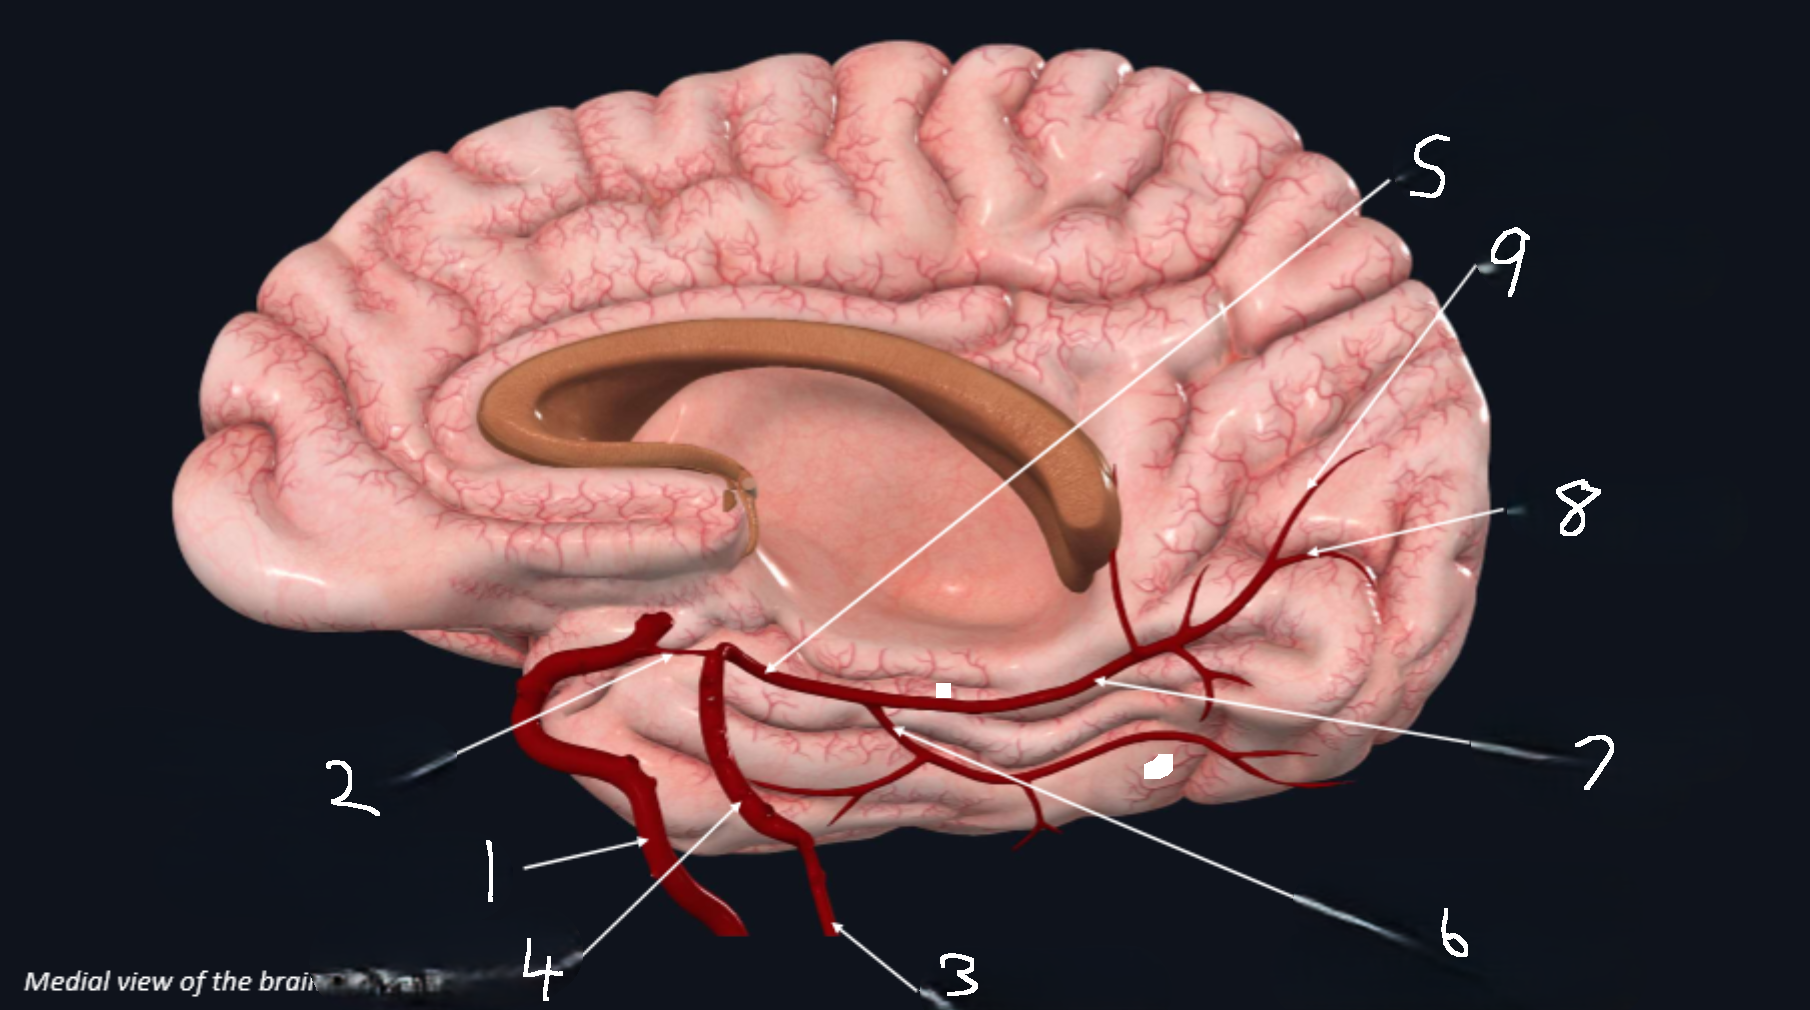

What is 1?

internal carotid artery

What is 2?

anterior cerebral artery

What is 3?

frontopolar artery

What is 4?

pericallosal artery

What is 5?

callosomarginal artery

What is 6?

corpus callosum